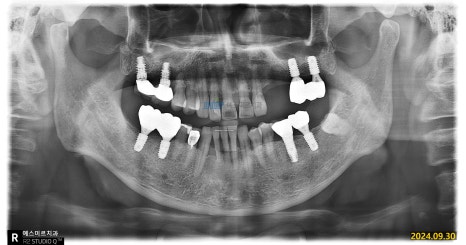

📍 내원 당시 상태

환자분은 수년 전 다른 병원에서 임플란트 치료를 받으셨는데,

최근 들어 임플란트 주변 잇몸이 자주 붓고 흔들리다가 통증이 반복돼 내원하셨습니다.

정밀 촬영과 검진 결과,

기존 임플란트 픽스처(뿌리)에 염증이 함께 발생한 상태였고

주변 골 손실도 상당해 제거 및 재수술이 필요한 상황이었습니다.